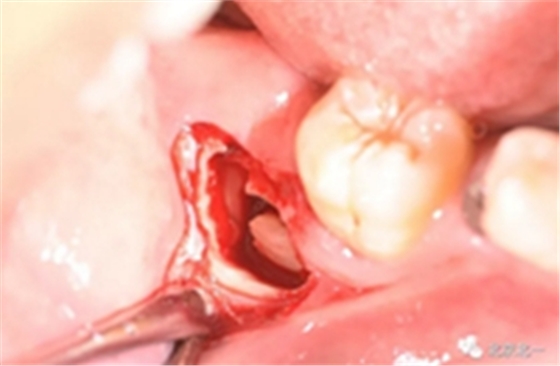

第二步:拔牙

切口设计关键点偏颊侧。

去骨:原则暴露最大周径线即可, 尽可能少去骨, 微创拔除。

截冠:有丝分裂至关重要。 保证微创下拔除智齿。